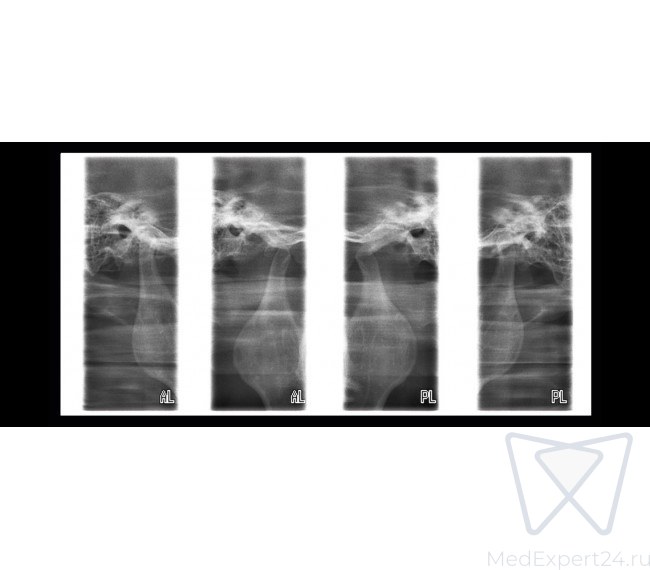

- Программа PA-вращающегося синуса,